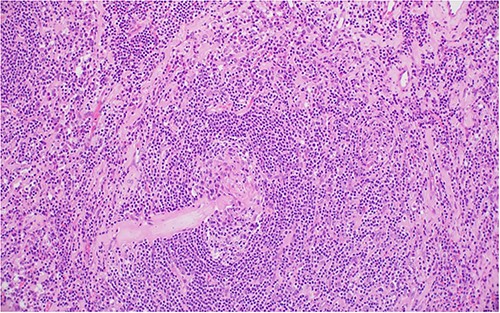

The patient underwent right laparoscopic adrenalectomy with a transperitoneal approach. A dark yellow tumor measuring 11 × 7 × 3.5 cm was removed en bloc (Fig. 2). Postoperative convalescence was uneventful and the patient was discharged home after 2 days, with discontinuation of antihypertensive medications. Microscopic examination revealed a mixed hyaline vascular and plasma cell variant type of Castleman lymphadenopathy (Figs 3 and 4). Immunohistochemistry showed a mixed pattern of CD20 and CD3, IgD that highlighted the expanded mantle zones and CD138-positive plasma cells that showed polytypic expression of Kappa and lambda immunoglobulin light chains. Immunostaining for Human herpesvirus 8 (HHV-8) was positive. A diagnosis of a unicentric mixed variant of Castleman lymphadenopathy was made.

(A), Regressed germinal center shows hyalinized blood vessels, dendritic cells and mantle zone forming an ‘onion skin’ arrangement; (B), the hyalinized blood vessels together with the atretic follicles and concentric mantle zone import a ‘lollipop’ appearance.